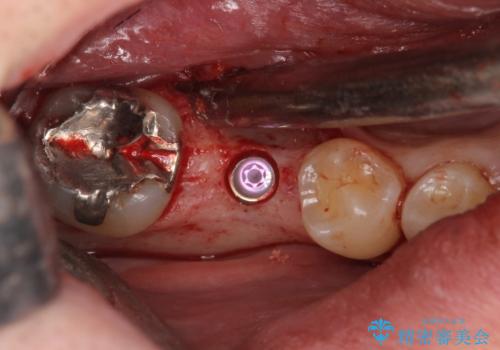

手術が怖いとのことで、外科手術時には静脈麻酔を行い、眠っている間に手術が終わるようにしました。

インプラントの術式は比較的単純で、難しくないですが、予後を見据えて角化歯肉を増やす手間をかけることが大変重要です。

インプラント手術時に同時に親知らずの抜歯も行い、腫れや痛みなどを1度で終わらせるようにしました。